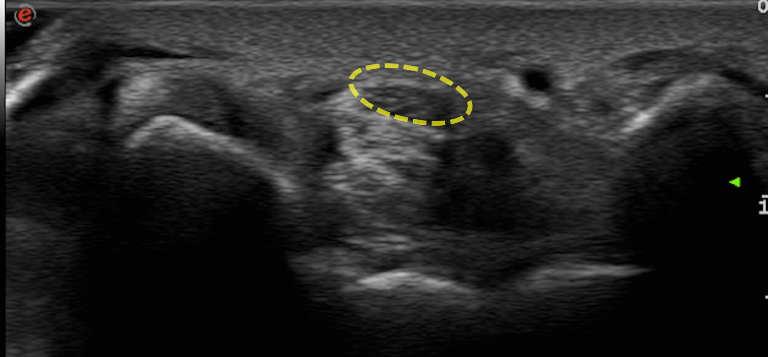

常用的物理儀器治療可以提供症狀一定程度的緩解,但還是會建議搭配手腕副木支架使用並定期追蹤。如果手指麻的症狀沒有改善,甚至進入到無力的狀況時,可能就要考慮更進一步的侵入性治療。可以局部注射類固醇或是在高階超音波影像導引下進行神經解套注射,將正中神經與周圍纏繞的軟組織分離。腕隧道症候群的病人在超音波下常可見腫脹的神經以及上下方壓迫的組織,解套注射即是針對壓迫處,利用注射液將壓迫組織與神經分離。